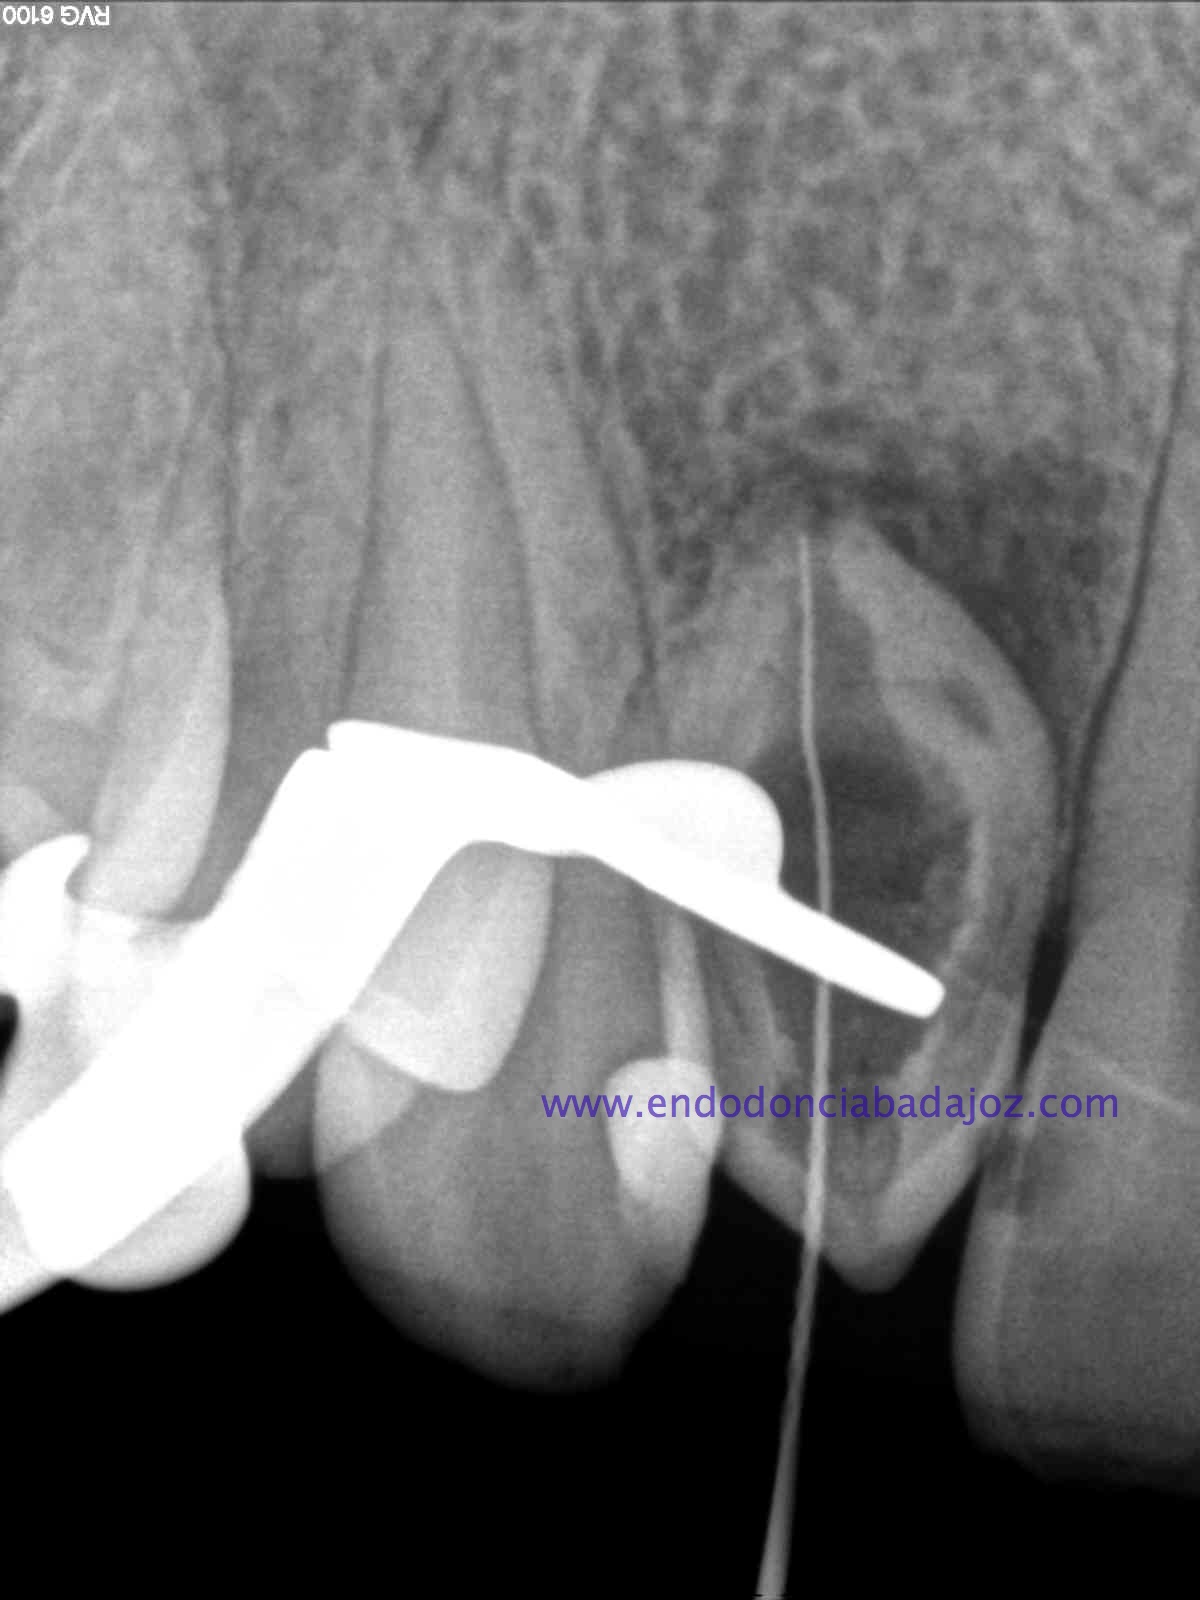

Nuestro caso, se trataba de esta pieza con necrosis pulpar con afectación periapical que presentaba una vía de drenaje (fístula). Esta radiografía muestra el camino de la fístula a la lesión apical.

Se planteó el caso con una apertura del mismo y tratamiento de todo el conducto con puntas de ultrasonido desbridando las paredes e intentando no eliminar demasiado tejido dentinario. El primer paso sería conseguir una permeabilización del conducto: